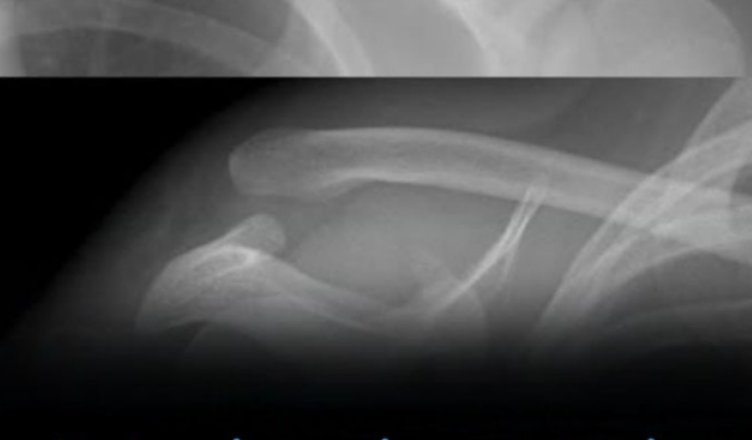

Kruchość kości: o czym zbyt często zapominamy

Mało kto wie: napoje gazowane, zwłaszcza cola, mogą wpływać na wytrzymałość naszych kości. Nie bezpośrednio ze względu na konkretny składnik, ale raczej dlatego, że zastępują inne napoje bogate w wapń, takie jak mleko czy wzbogacone wapniem napoje roślinne . U nastolatków i młodych dorosłych taka zamiana może utrudniać budowę mocnych kości. Natomiast u dorosłych może przyczyniać się do zwiększonej kruchości kości w dłuższej perspektywie .